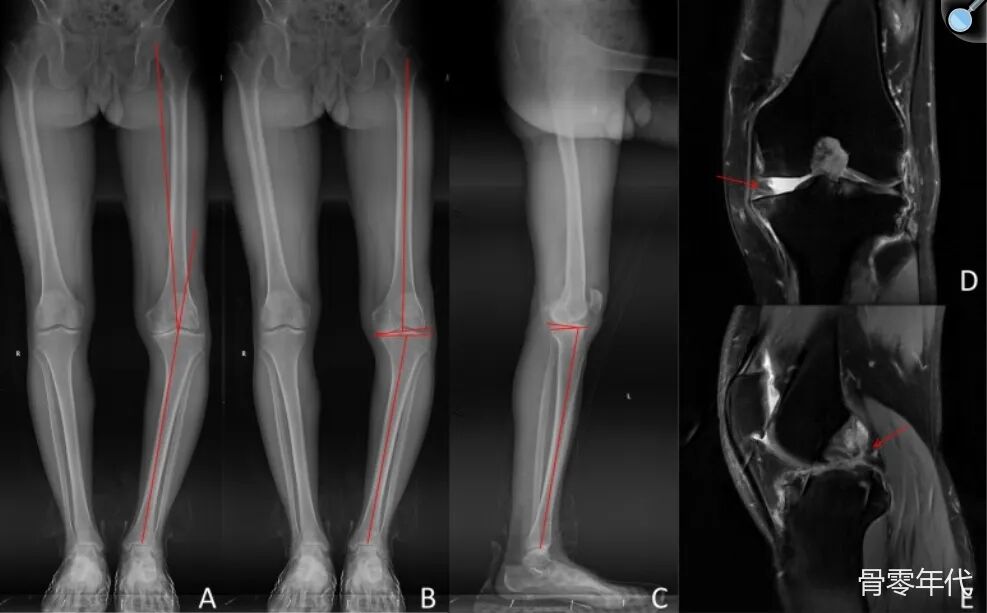

影像学表现